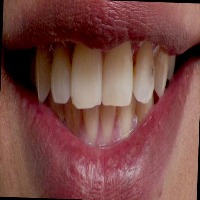

teeth Computer Vision Project

Classes (19)

Teeth are annotated in COCO Segmentation format.

The dataset includes 127 images.